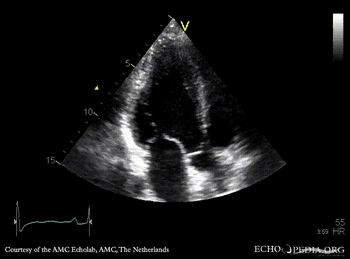

Case 42